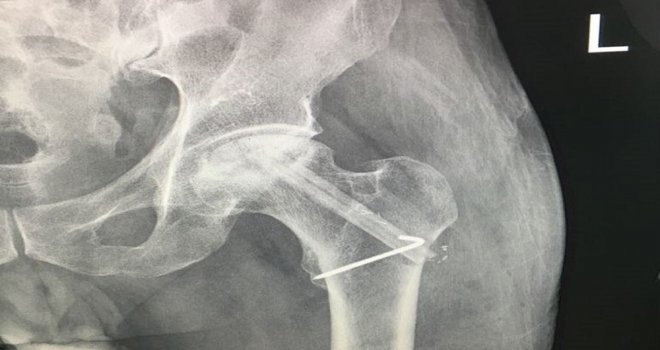

Sivasta Cumhuriyet Üniversitesi Hastanesine kalça kemiği çürümesi şikayetiyle başvuran bir hastanın ayak kemiği ameliyatla kalçasına nakledildi. Başarılı geçen operasyon hakkında bilgi veren Ortopedi Travmatoloji Ana Bilim Dalı Öğretim Üyesi Dr. Özhan Pazarcı,Hastalığın erken evrelerinde bu hastalara ameliyatsız tedavi uygulanırken ileri ki evrelerde kalça protezi uygulanıyor. Sağlıklı kalça kemiğini korumak ve yeniden kazanmak için yapılan bir ameliyat var. Bu da ileri mikro cerrahi teknik gerektiren canlı kemik nakli ameliyatıdır. Burada hastanın kaval kemiğini alıp damarıyla birlikte kalça kemiğine naklediyoruz. Böylece hasta sağlıklı kalça kemiğine tekrar kavuşuyor. Bu, ekip gerektiren ileri mikro cerrahi tekniklerine hakimiyet gerektiren bir ameliyattır. Bu ameliyatı Plastik Cerrahiden Dr. Handan hocayla birlikte gerçekleştirdik. Bu operasyon bildiğim kadarıyla hastanemizde ilk defa yapıldı. Bu ameliyatlarda yüzde seksen beş oranında başarı sağlanıyor. Daha sonra yine kalça protez ameliyatına gitmelerine gerek kalmıyor. Hastamız altmış yaşında uzun süredir kalçasından muzdarip bir hastaydı. Canlı kemik nakliyle hastamızın sağlığına kavuşmasını sağladık dedi

Kalça kemiğinin çürümesinin sık görüldüğünü anlatan Dr. Pazarcı, Kalça kemiğinin çürümesi toplumda azımsanmayacak şekilde görülüyor. Özellikle alkol tüketimi, sigara tüketimi, obezite, düşme ve travma gibi durumlarda bu hastalık görülüyor. Bu hastaların yakalandığı evrelere göre tedavi uygulanıyor. Kalça protezi geri dönüşü olmayan bir ameliyat. Son evreden önce bu hastaları kurtarmak için bu ameliyatın hastanemizde yapılması bu anlamda çok önemli. Kalça osteonekrozu, öncelikle hastalarda kalçada ağrı şikayeti ile başlar, daha sonra hareket kısıtlılığı, açıp kapamada kısıtlılık, yürüme güçlüğü şikayetiyle bize başvururlar ifadelerini kullandı.

Plastik ve Rekonstrüktif Cerrahi Ana Bilim Dalı Dr. Öğretim Görevlisi Handan Derebaşınlıoğlu ise Bu, ekip işiyle yapılan bir ameliyat. Ortopedi gerekli yeri hazırlıyor, biz de kaval kemiğini damarıyla beraber alıp damarları birbirine dikiyoruz. Böylece damarsız olan, kanlanmayan bir dokudan daha iyi bir iyileşme sağlıyoruz. Bacağında hastanın sadece ameliyata bağlı olarak bir iz kalıyor, onun dışında bir sıkıntı yaşamıyoruz. Tabii çok kolay bir ameliyat değil. Eğitim alınması gerekir, belli bir birikiminizin olması gerekir. Üniversite hastanemizde kalçaya kaval kemiğin nakledilmesi ilk defa yapılıyor şeklinde konuştu.